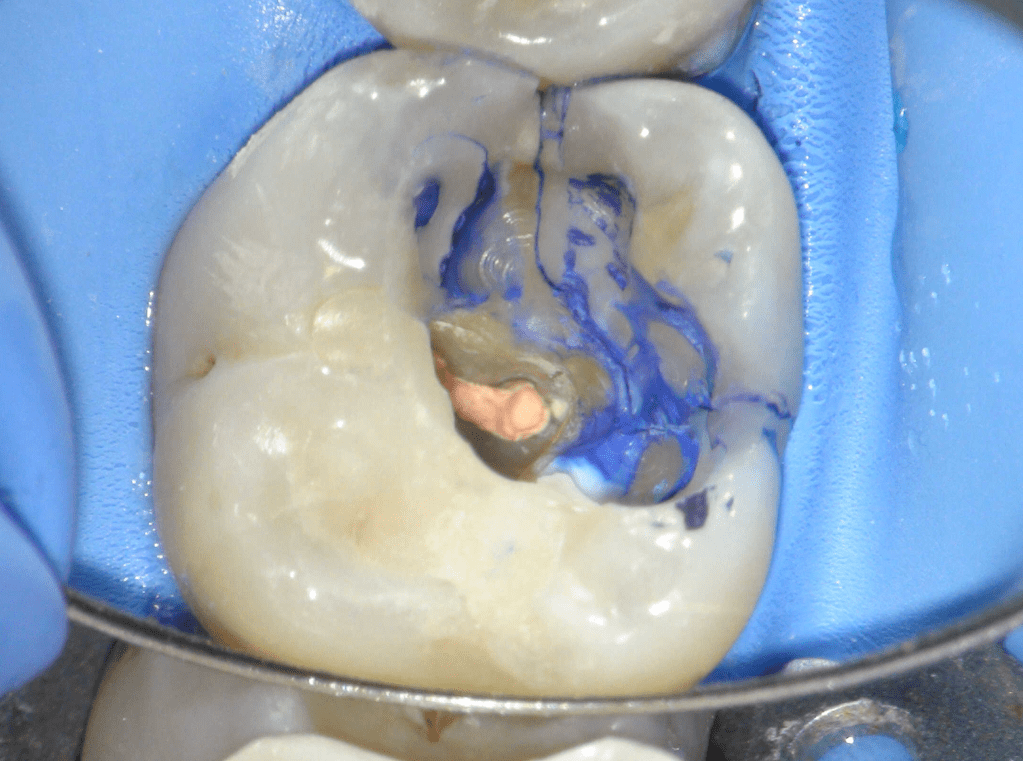

Reco pre-endo gingivectomái, pared yuxtaosea